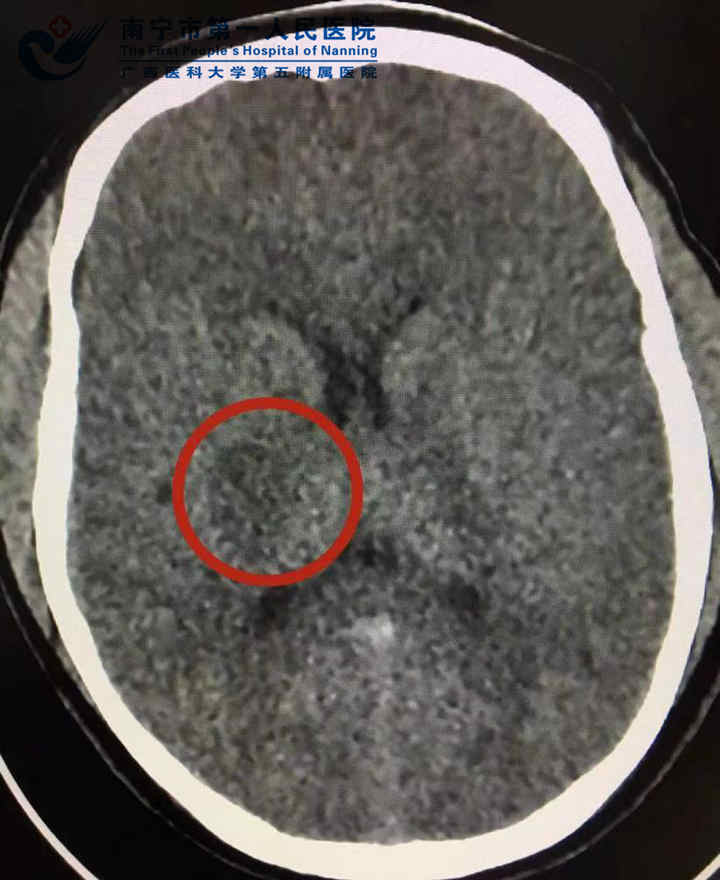

原某某,18岁,布满激情、活力的青春年华,正是人生感受多彩生命、编织人生梦想的时候,然后,他却遇到不该这个年纪遇到的事情,这怎么回事呢?12月25日,我院神经内科收治了一名左上肢不能抬起、不能持物,左下肢不能独立行走约13小时的18岁青年男性患者,经我院卒中团队评估,患者已超最佳静脉溶栓时间窗,立即联系放射影像科进一步完善一站式多模式影像检查。CT平扫显示右侧基底节区低密度梗死灶(红色圆圈所示)CTA提示右侧大脑中动脉重度狭窄(红...